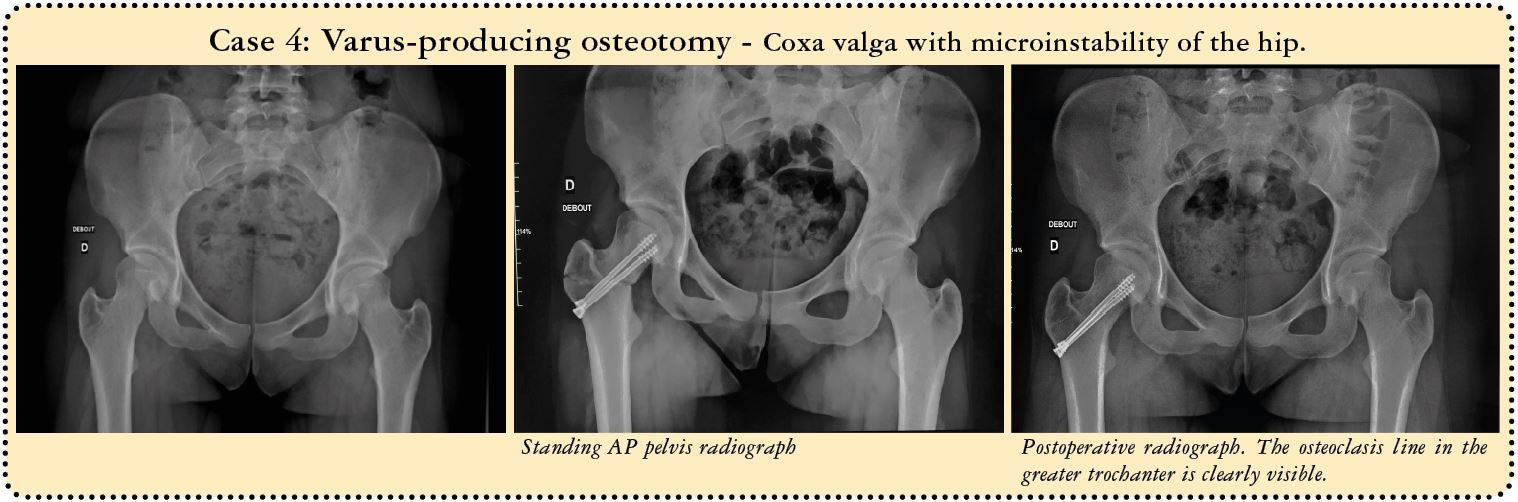

For a varus-producing osteotomy, a wedge can be removed from the medial base, matching the desired angle of correction. The higher the line, the more accurate the wedge calculations must be because it is all to easy to exaggerate the valgus correction by having the line too close to the neck. The preoperative planning must be just as meticulous as for the traditional technique. We use new computer tools to simplify and even simulate this type of surgery.

Nine of the corrections involved a varus-producing osteotomy, five a valgus-producing osteotomy and one femoral derotation for excessive femoral anteversion.

Two patients underwent a simultaneous periacetabular osteotomy. In one of these two cases, involving a young 27-year old patient, the periacetabular and varus osteotomy were accompanied by a cartilage transplantation using the mosaicplasty technique with anterior femoral dislocation. All three procedures were of course performed through the same portal.